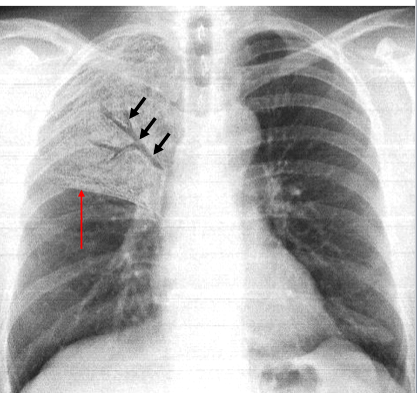

Classiquement, la température est de 38 à 38,5°C c) Signes physiques En dehors de la tachycardie, l'examen peut retrouver un syndrome de condensation pulmonaire et celui d'un épanchement pleural dont la ponction ramène un liquide sérohémorragique, riche en protides, de formule mixte 2) Atypiques. 95 Semio11indb 95 07. Perlée petites perles expectorées à la fin de la crise d’asthme (crachat perlé de Laennec, riches en éosinophiles) Moules bronchiques fibrineux ou bouchons muqueux qui ont moulé la bronche (petits cylindres fongiques) rencontrés parfois dans l’asthme ou l’aspergillose bronchopulmonaire allergique.